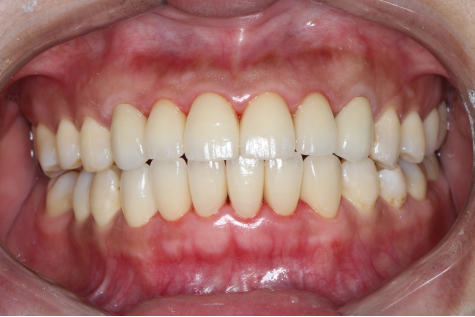

全瓷修复后的牙齿

不到一个小时,牙龈上的黑线消失了,牙齿又恢复了往日的风采,董女士开心的笑了,她说道:"以后又可以开心的和客户交谈了,感谢熊医生,感谢麦芽口腔先进的技术,以后一定好好的护理自己的牙齿!"